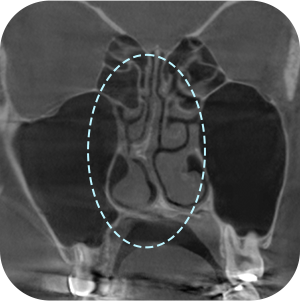

确认之前手术 的假体情报

确认鼻中隔弯曲症等 功能性问题

确认目前现假体 的位置

一定要拍鼻子CT吗?

A因为是修复手术,所以要更精密地诊断!

鼻部修复手术需要彻底的分析非常重要

通过3D-CT扫描 准确的分析! - 03